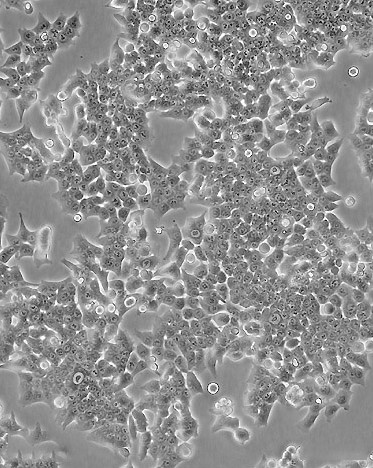

RPMI2650人鼻中隔鳞状癌细胝/div>

RPMI2650人鼻中隔鳞状癌细胞图?></a></div>    <span style=

这株细胞来自1962年一名患有鼻中隔间变性鳞状细胞癌?2岁男子的胸腔积液

细胞类型

上皮皃/p>

生长方式

贴壁